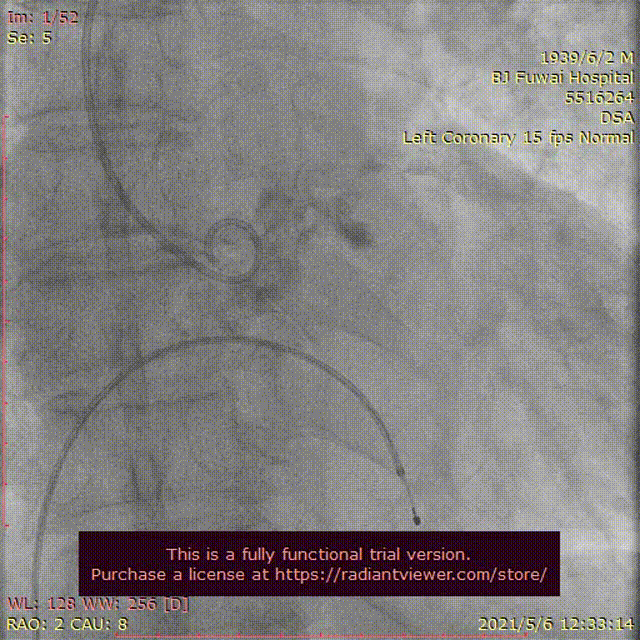

图3患者经导管主动脉瓣置换术及围术期操作

A:主动脉根部造影;B:23 mm球囊预扩张;C:26型号VenusA瓣膜植入;D:26型号VenusA“瓣中瓣”位置良好,少量瓣周漏;E和F:术前及术后经导管跨瓣压差;G:肘正中静脉留置针;H:患者全程清醒状态。